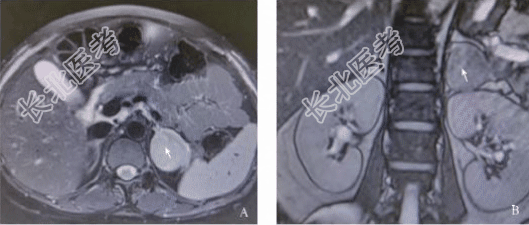

辅助检查:血皮质醇(8:00am)1537nmol/L、血皮质醇(16:00pm)1505nmol/L,昼夜节律消失;1mg地塞米松抑制试验后血皮质醇(8:00am)1544nmol/L,不能被抑制。血促肾上腺皮质激素(ACTH)(8:00am)1.0pg/ml、ACTH(16:00pm)1.0pg/ml。空腹血糖3.91mmol/L、餐后2h血糖6.1mmol/L。血钾2.95mmol/L、血钠139.6mmol/L、血氯101.3mmol/L。血常规:白细胞6.8×10⁹/L、红细胞3.53×10¹²/L、血红蛋白114g/L、血小板96×10⁹/L。影像学检查:磁共振成像(MRI)示左侧肾上腺区可见3.9cm×4.3cm×4.6cmT1WI等信号、T2WI欠均匀占位(图2);垂体Rathke’s囊肿。